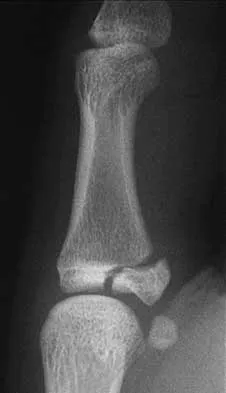

Question 48High Yield

An 11-year-old boy has had a fever and pain and swelling over the lateral aspect of his right ankle for the past 3 days. Examination reveals warmth, swelling, and tenderness over the lateral malleolus, and he has a temperature of 103.2 degrees F (39.5 degrees C). Laboratory studies show a WBC count of 13,200/mm3 with 61% neutrophils, an erythocyte sedimentation rate of 112 mm/h, and a C-reactive protein of 15.7. Radiographs and a T2-weighted MRI scan are shown in Figures 13a through 13c. Aspiration yields 1 mL of purulent fluid. Management should now consist of

Explanation

The initial signs and symptoms of acute hematogenous osteomyelitis vary widely but usually include fever, bone pain, and impaired use of the involved extremity. In lower extremity infections, the child may limp or refuse to walk. Examination often reveals bone tenderness. In more advanced cases, erythema, warmth, and swelling may be present. The WBC and neutrophil counts are not always elevated, but the erythocyte sedimentation rate will be abnormal in more than 90% of patients. When the infection is diagnosed early, before a subperiosteal abscess has formed, antibiotics alone may be adequate to treat the infection. This patient has a more advanced infection, however, with the MRI scan revealing a subperiosteal abscess that was confirmed by aspiration. When an abscess is present, surgical drainage is generally indicated to remove devitalized tissue and to enhance the efficacy of the antibiotics. Further studies, such as bone or indium scans, are not necessary and will delay definitive treatment. Scott RJ, Christofersen MR, Robertson WW Jr, et al: Acute osteomyelitis in children: A review of 116 cases. J Pediatr Orthop 1990;10:649-652.